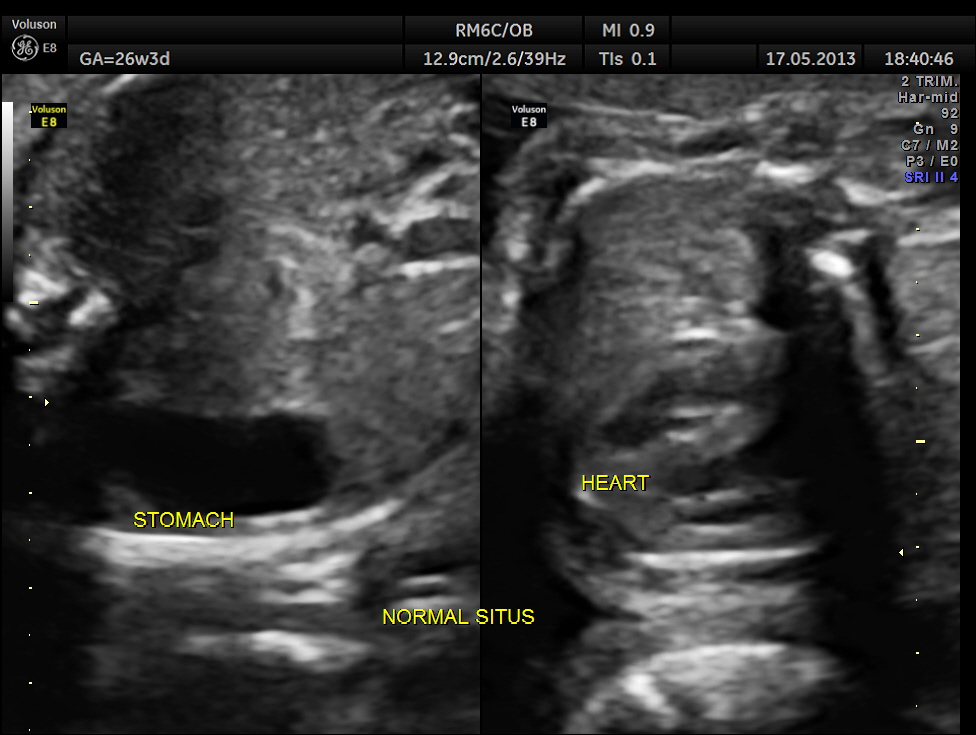

The abdominal images are given below.

This fetus did not show any oro-facial clefts ; heart and spine appeared normal.